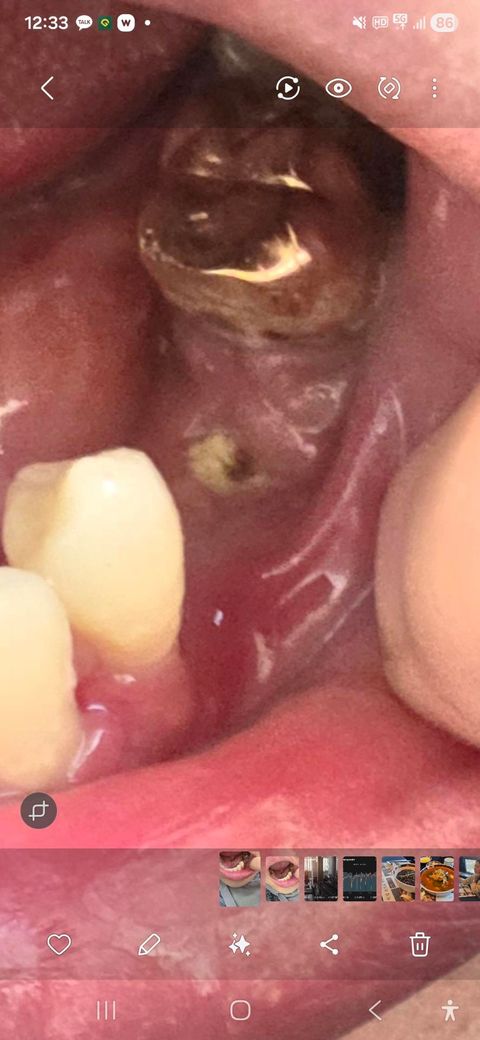

임플란트 잇몸뼈이식후 실밥제거 하고 뼛가루가 조금 나옵니다

좀전에 글을 올렸는데 측면 사진 하나 더 올려봅니다

잘 치유가 되고 있는건지 가운데랑은 잘 아물었는데 바깥쪽이 아직 아물지가 않았네요 통증이나 고름등은 현재 없습니다

아직 완전히 아문 상태는 아닙니다 해당 부위 위생관리를 좀 더 신경써서 해주시면 치유에 도움이 됩니다